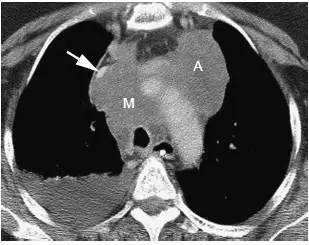

图12 小细胞肺癌

对比增强CT 显示典型的小细胞肺癌广泛纵隔淋巴结增大,气管前淋巴结增大致上腔静脉( 箭头) 向前移位并明显狭窄,可见前纵隔淋巴结融合的大肿块,右侧可见胸腔积液